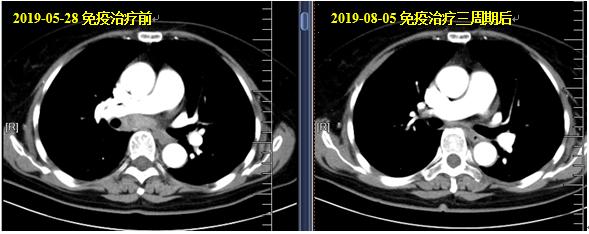

采用新抗原个体化纳米疫苗联合PD-1抗体治疗:行环磷酰胺+个体化疫苗+信迪利单抗方案治疗3周期,并予注射疫苗总共六次,未见明显不良反应。可测量病灶:纵膈肺门淋巴结、右肺小结节(原有的盆腔、外阴病灶自放疗后维持CR)。疗效评价:接近CR,血肿瘤指标均降至正常。